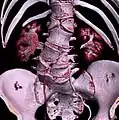

Transitional vertebrae

Short ribs at the first lumbar vertebra, which is thus a transitional vertebra, since lumbar vertebrae normally do not have ribs attached to them.

Transitional vertebrae have the characteristics of two types of vertebra. The condition usually involves the vertebral arch or transverse processes. It occurs at the cervicothoracic, thoracolumbar, or lumbosacral junction. For instance, the transverse process of the last cervical vertebra may resemble a rib. A transitional vertebra at the lumbosacral junction can cause arthritis, disk changes, or thecal sac compression. Back pain associated with lumbosacral transitional vertebrae (LSTV) is known as Bertolotti's syndrome. One study found that male German Shepherd Dogs with a lumbosacral transitional vertebra are at greater risk for cauda equina syndrome, which can cause rear limb weakness and incontinence.[10]